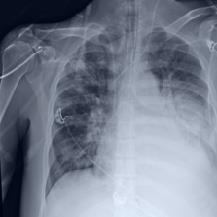

Thoracic disease detection from chest radiographs using deep learning methods has been an active area of research in the last decade. Most previous methods attempt to focus on the diseased organs of the image by identifying spatial regions responsible for significant contributions to the model's prediction. In contrast, expert radiologists first locate the prominent anatomical structures before determining if those regions are anomalous. Therefore, integrating anatomical knowledge within deep learning models could bring substantial improvement in automatic disease classification. This work proposes an anatomy-aware attention-based architecture named Anatomy X-Net, that prioritizes the spatial features guided by the pre-identified anatomy regions. We leverage a semi-supervised learning method using the JSRT dataset containing organ-level annotation to obtain the anatomical segmentation masks (for lungs and heart) for the NIH and CheXpert datasets. The proposed Anatomy X-Net uses the pre-trained DenseNet-121 as the backbone network with two corresponding structured modules, the Anatomy Aware Attention (AAA) and Probabilistic Weighted Average Pooling (PWAP), in a cohesive framework for anatomical attention learning. Our proposed method sets new state-of-the-art performance on the official NIH test set with an AUC score of 0.8439, proving the efficacy of utilizing the anatomy segmentation knowledge to improve the thoracic disease classification. Furthermore, the Anatomy X-Net yields an averaged AUC of 0.9020 on the Stanford CheXpert dataset, improving on existing methods that demonstrate the generalizability of the proposed framework.